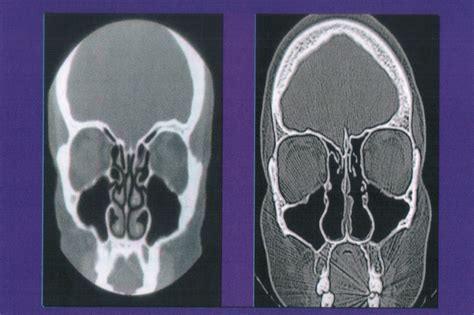

When these structures are over-resected, the nasal cavity becomes overly spacious. Despite this "empty" space, patients paradoxically feel a severe sensation of nasal obstruction, often described as the inability to get enough air into the lungs. This phenomenon is likely due to the loss of sensory feedback and the disruption of normal airflow patterns within the nose.

Diagnosing Empty Nose Syndrome is inherently difficult. Because standard clinical measures, such as rhinomanometry, often show increased airflow (indicating a “patent” airway), traditional tests may suggest the patient is fine. However, the patient’s subjective experience contradicts these findings. Physicians must rely heavily on patient history and a thorough examination of the nasal cavity’s structure to diagnose the condition.